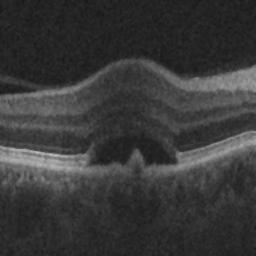

The qualitative results of the proposed system is shown in the Fig. 3. The detection task is evaluated using Area Under the Curve(AUC) metric and the segmentation task is evaluated using Dice Coefficient(DC) metric and the results are presented in Table1

|

|

| (d) De-noised OCT slice | (e)Predicted fluid region | (f)Manual fluid segmentation |

|

|

|

| (g) De-noised OCT slice | (h)Predicted fluid region | (i)Manual fluid segmentation |